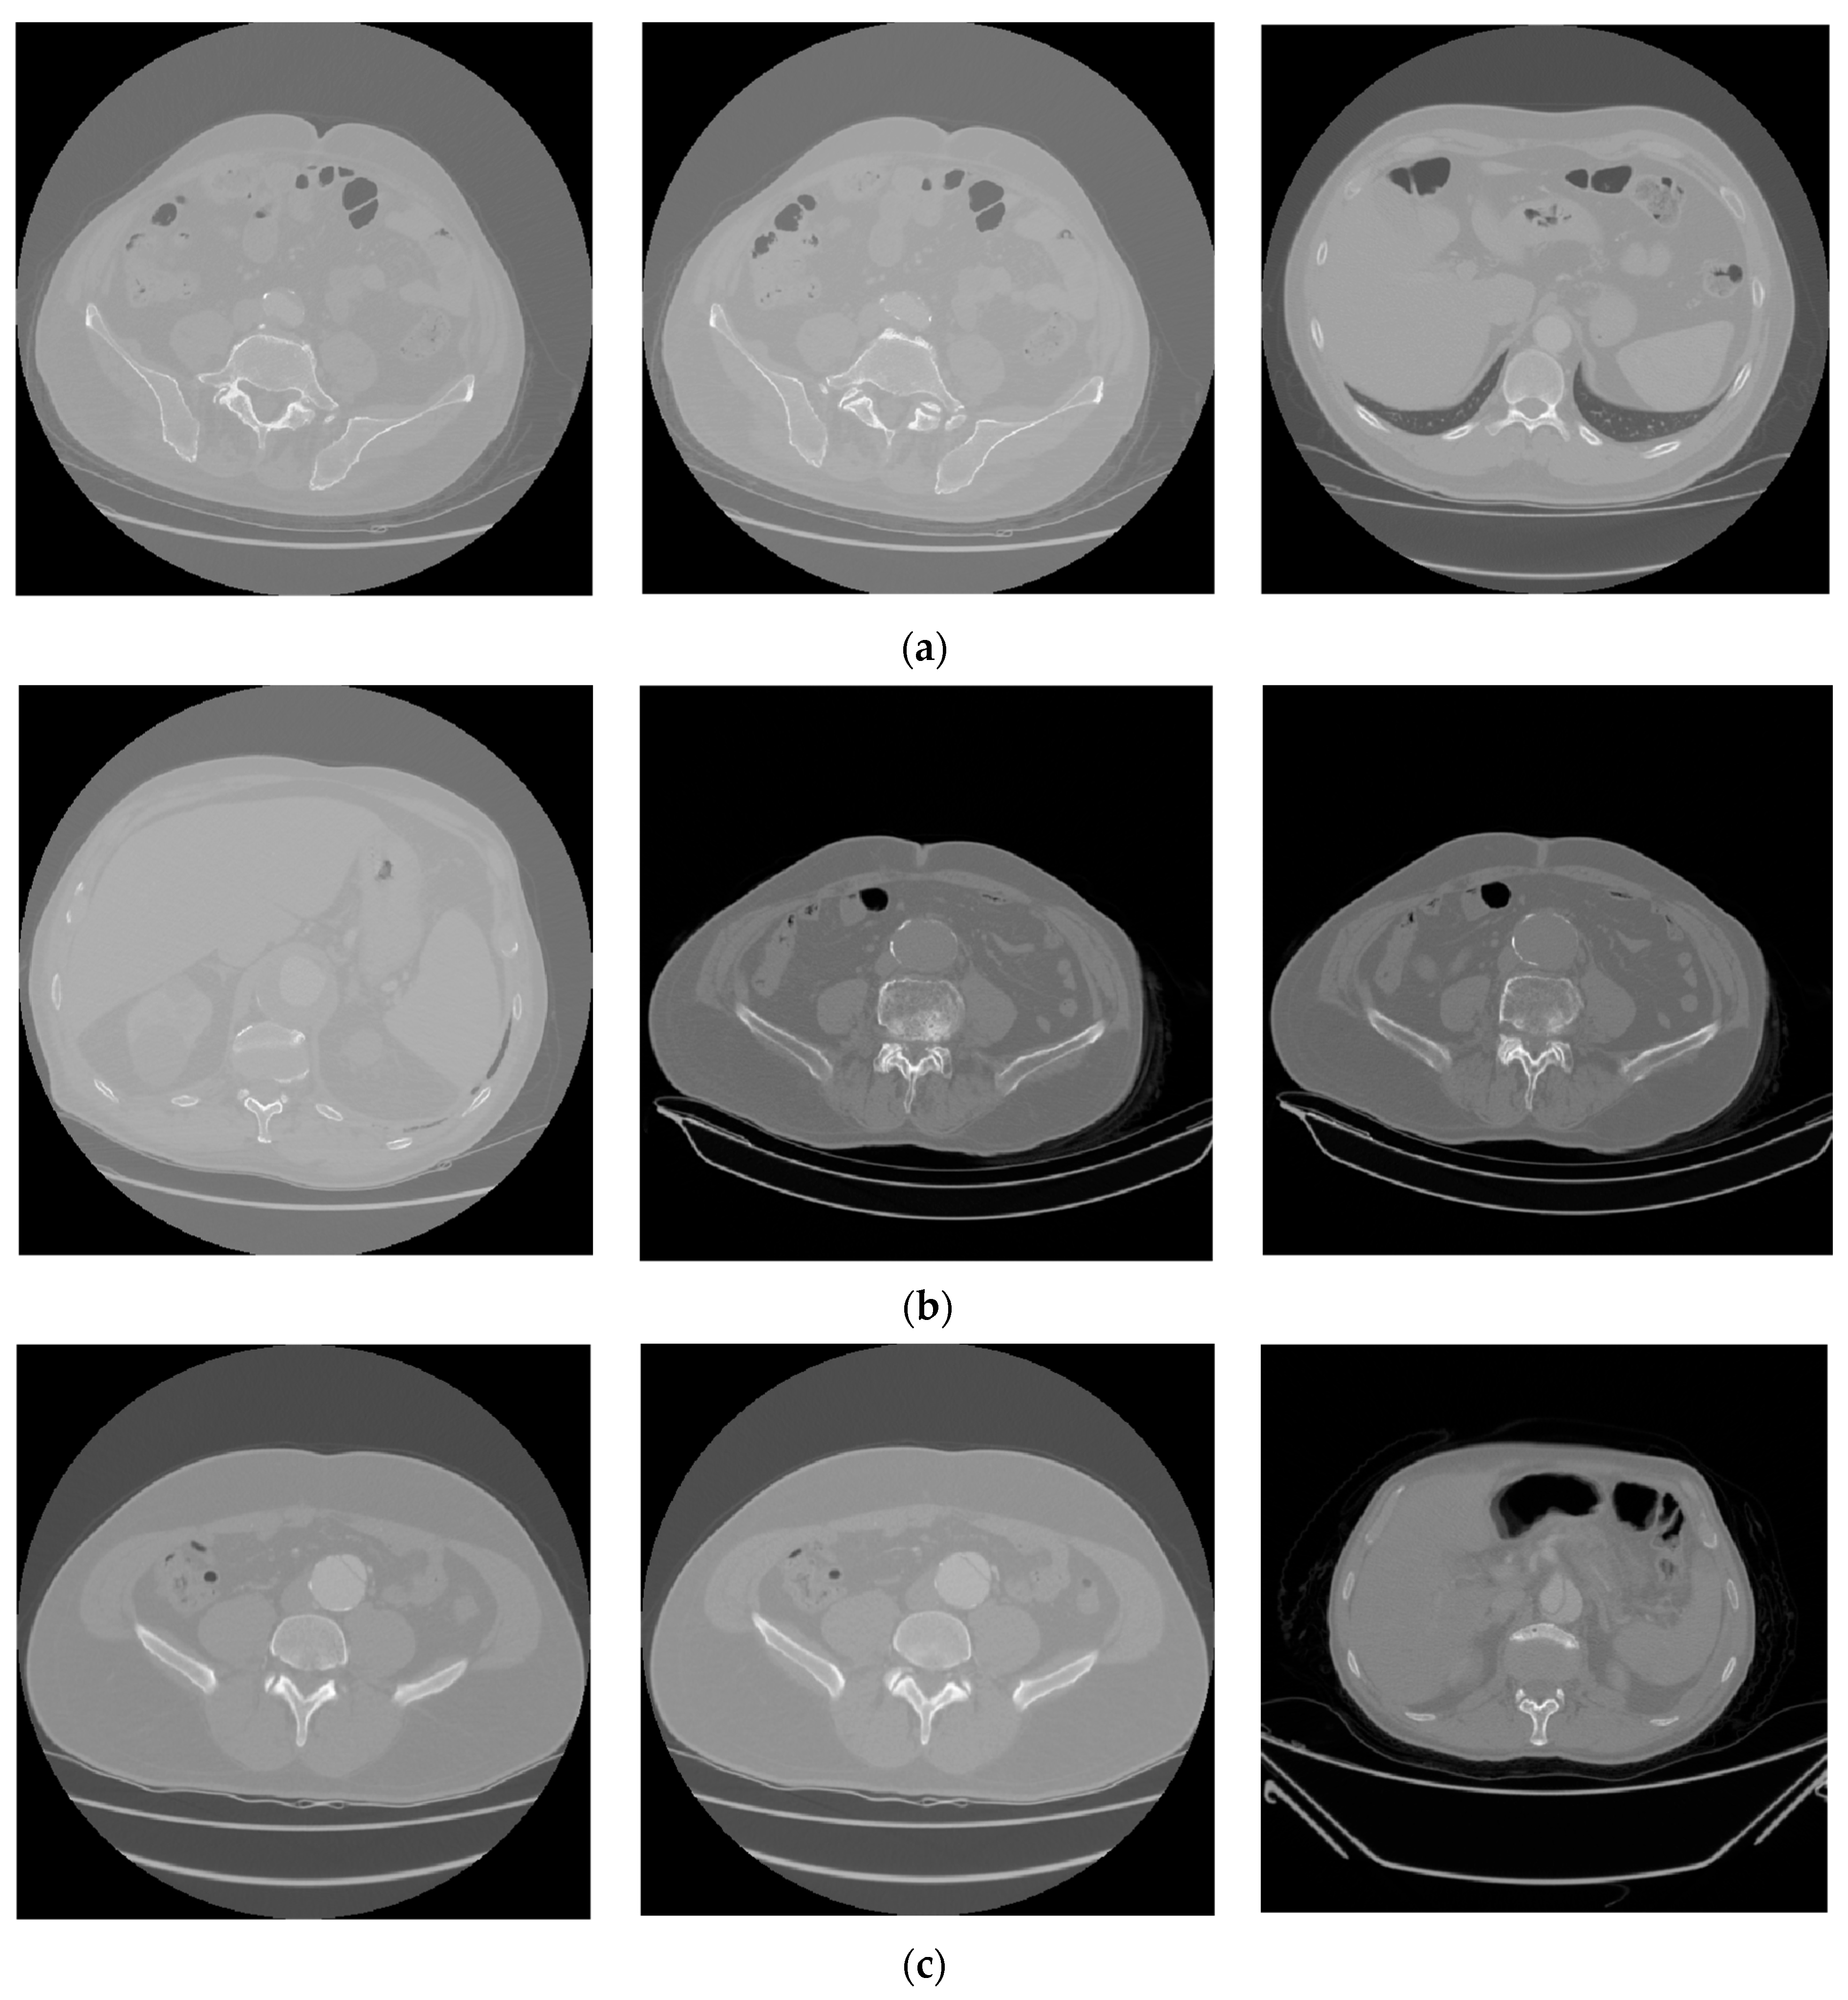

3.1. Dataset